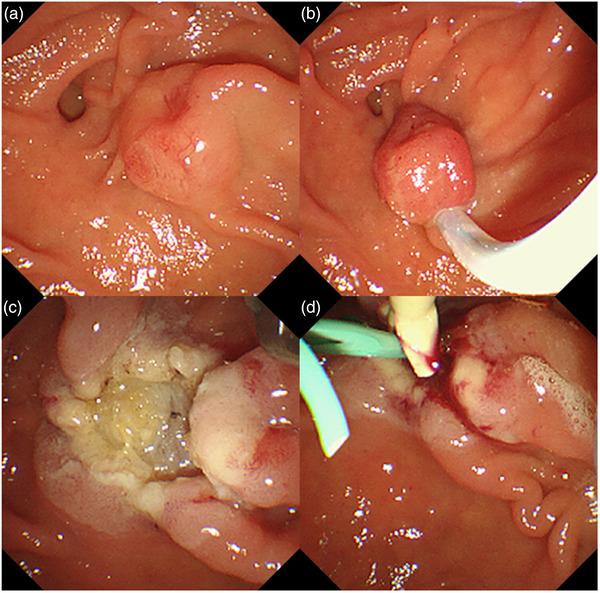

We report the case of a 62-year-old female with a 6.3-mm low-grade neuroendocrine tumor of the ampulla of Vater, who underwent an endoscopic papillectomy. An endoscopic papillectomy was performed without complications. In the 26 months of follow-up, no local recurrence or metastasis occurred. Endoscopic treatment of ampullary neuroendocrine tumors is controversial. However, endoscopic papillectomy may be considered a treatment option if neuroendocrine tumors are small (<10 mm), have a low grade (G1), or do not have muscle layer or bile duct invasion.

我们报告了一例62岁女性患者,其患有6.3毫米的 Vater壶腹低级别神经内分泌肿瘤,该患者接受了内镜下乳头切除术。手术过程顺利,未出现并发症。在26个月的随访中,未发生局部复发或转移。壶腹神经内分泌肿瘤的内镜治疗存在争议。然而,如果神经内分泌肿瘤较小(<10毫米)、级别较低(G1)或未侵犯肌层或胆管,内镜下乳头切除术可被视为一种治疗选择。